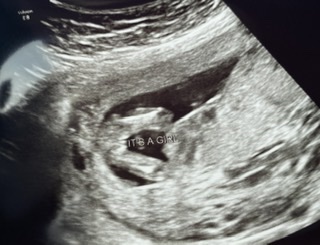

Hi! I had an elective ultrasound at 14 weeks and the tech was confident it is a girl based on both nub and potty shot. I swayed for a girl so praying she is right!! What do you think? P.s. sorry if these pictures are uploaded weird or doubles.. never done pictures before lol Attachment 42861Attachment 42862Attachment 42863Attachment 42862Attachment 42863Attachment 42864